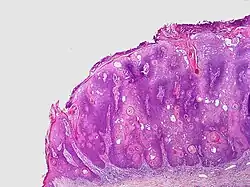

.jpg)

Visual diagnosis is made by the "stuck on" appearance, horny pearls or cysts embedded in the structure. Darkly pigmented lesions can be challenging to distinguish from nodular melanomas.[10] Furthermore, thin seborrheic keratoses on facial skin can be very difficult to differentiate from lentigo maligna even with dermatoscopy. Clinically, epidermal nevi are similar to seborrheic keratoses in appearance. Epidermal nevi are usually present at or near birth. Condylomas and warts can clinically resemble seborrheic keratoses, and dermatoscopy can be helpful to differentiate them. On the penis and genital skin, condylomas and seborrheic keratoses can be difficult to differentiate, even on biopsy.

A study examining over 4,000 biopsied skin lesions identified clinically as seborrheic keratoses showed 3.1% were malignancies. Two-thirds of those were squamous cell carcinoma.[11] To date, the gold standard in the diagnosis of seborrheic keratosis is represented by the histolopathologic analysis of a skin biopsy.[12]